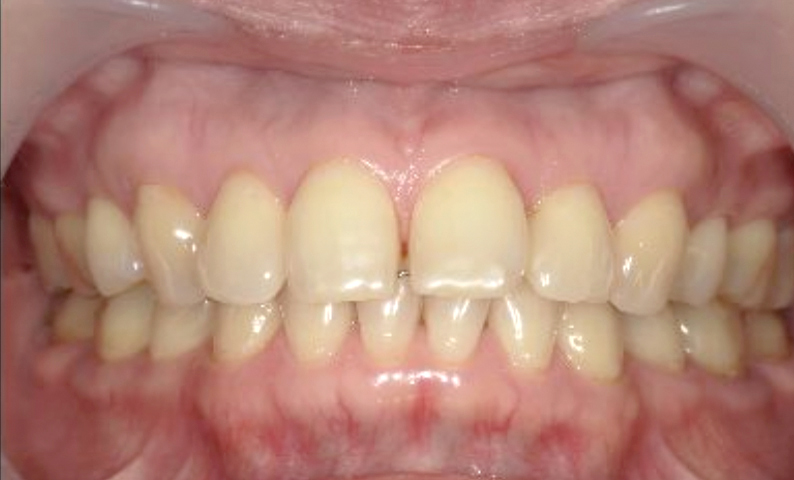

| 治療前 | 治療後 |

|---|---|

|